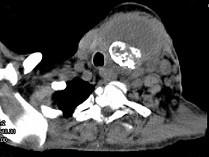

问题 女,64岁,发现双甲状腺肿大1月余,CT如图所示,最可能诊断为()

选项 A.结节性甲状腺肿 B.甲状腺腺瘤 C.甲状腺癌并淋巴结转移 D.甲状腺转移瘤 E.甲状腺结核

答案 C